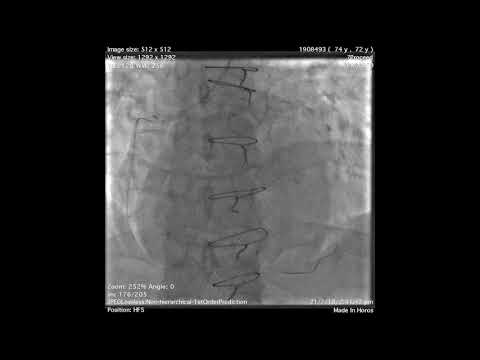

Completely Retrograde Wiring Technique in CTO intervention

Distal Anchoring Technique and SVG coiling: CTO solutions